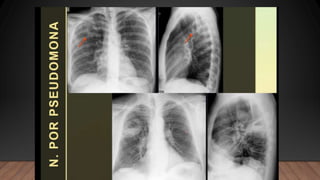

La neumonía causa un cuadro de condensación pulmonar producida por un exudado inflamatorio y proceso infeccioso que puede ser lobar, segmentario, intersticial, redondo o cavitario, siendo la forma lobar o alveolar la más común.